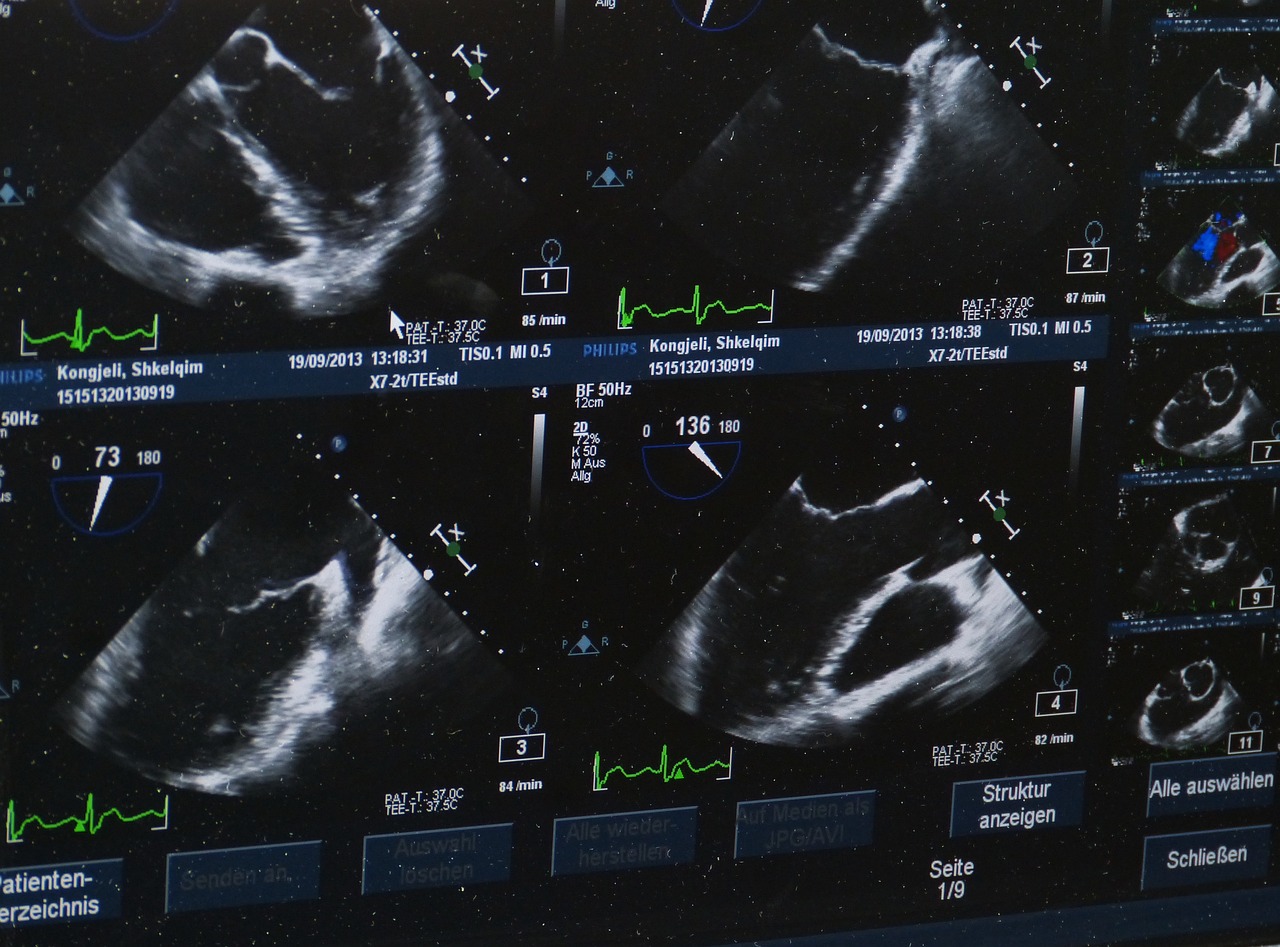

- 복부 초음파: 통증이나 황달이 있을 때 담석증과 구분하기 위해 1차적으로 시행합니다. 하지만 췌장이 깊숙이 있어 정확도가 낮을 수 있습니다.

- 내시경 초음파(EUS): 내시경으로 췌장을 가까이 관찰하며, 필요 시 조직검사를 동시에 진행합니다. 진단 정확도가 90% 이상입니다.